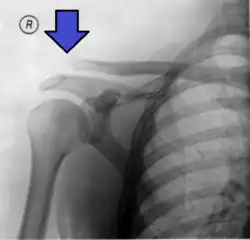

This is a more severe form of a type III injury, with the trapezial and deltoid fascia stripped off of the acromion as well as the clavicle. This is type III but with exaggeration of the vertical displacement of the clavicle from the scapula. There is a 2- to 3-fold increase in the coracoclavicular distance, causing such a severe displacement that the clavicle almost pierces the skin.[11] The humerus and scapula drop without having the clavicular strut to lift them, which manifests as a severely drooping shoulder.[11] This injury generally requires surgery.[5] Distinguishing between Type III and Type V separations on imaging can be unreliable.[12]